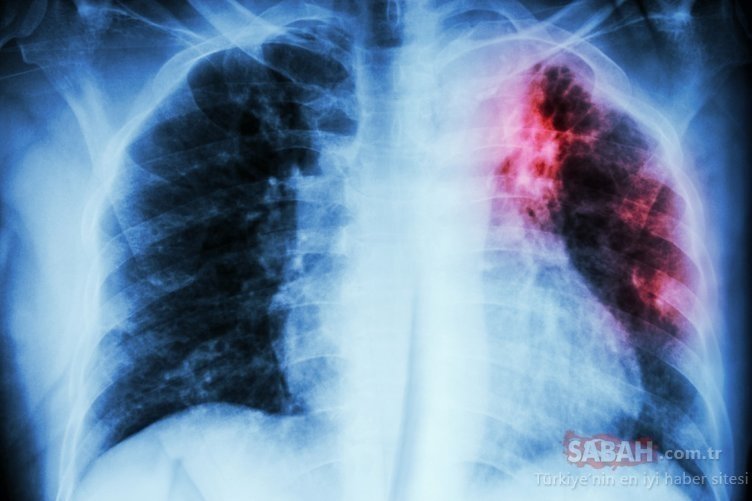

Akciğer kanseri belirtileri nelerdir! İşte Akciğer kanserinin belirtileri?